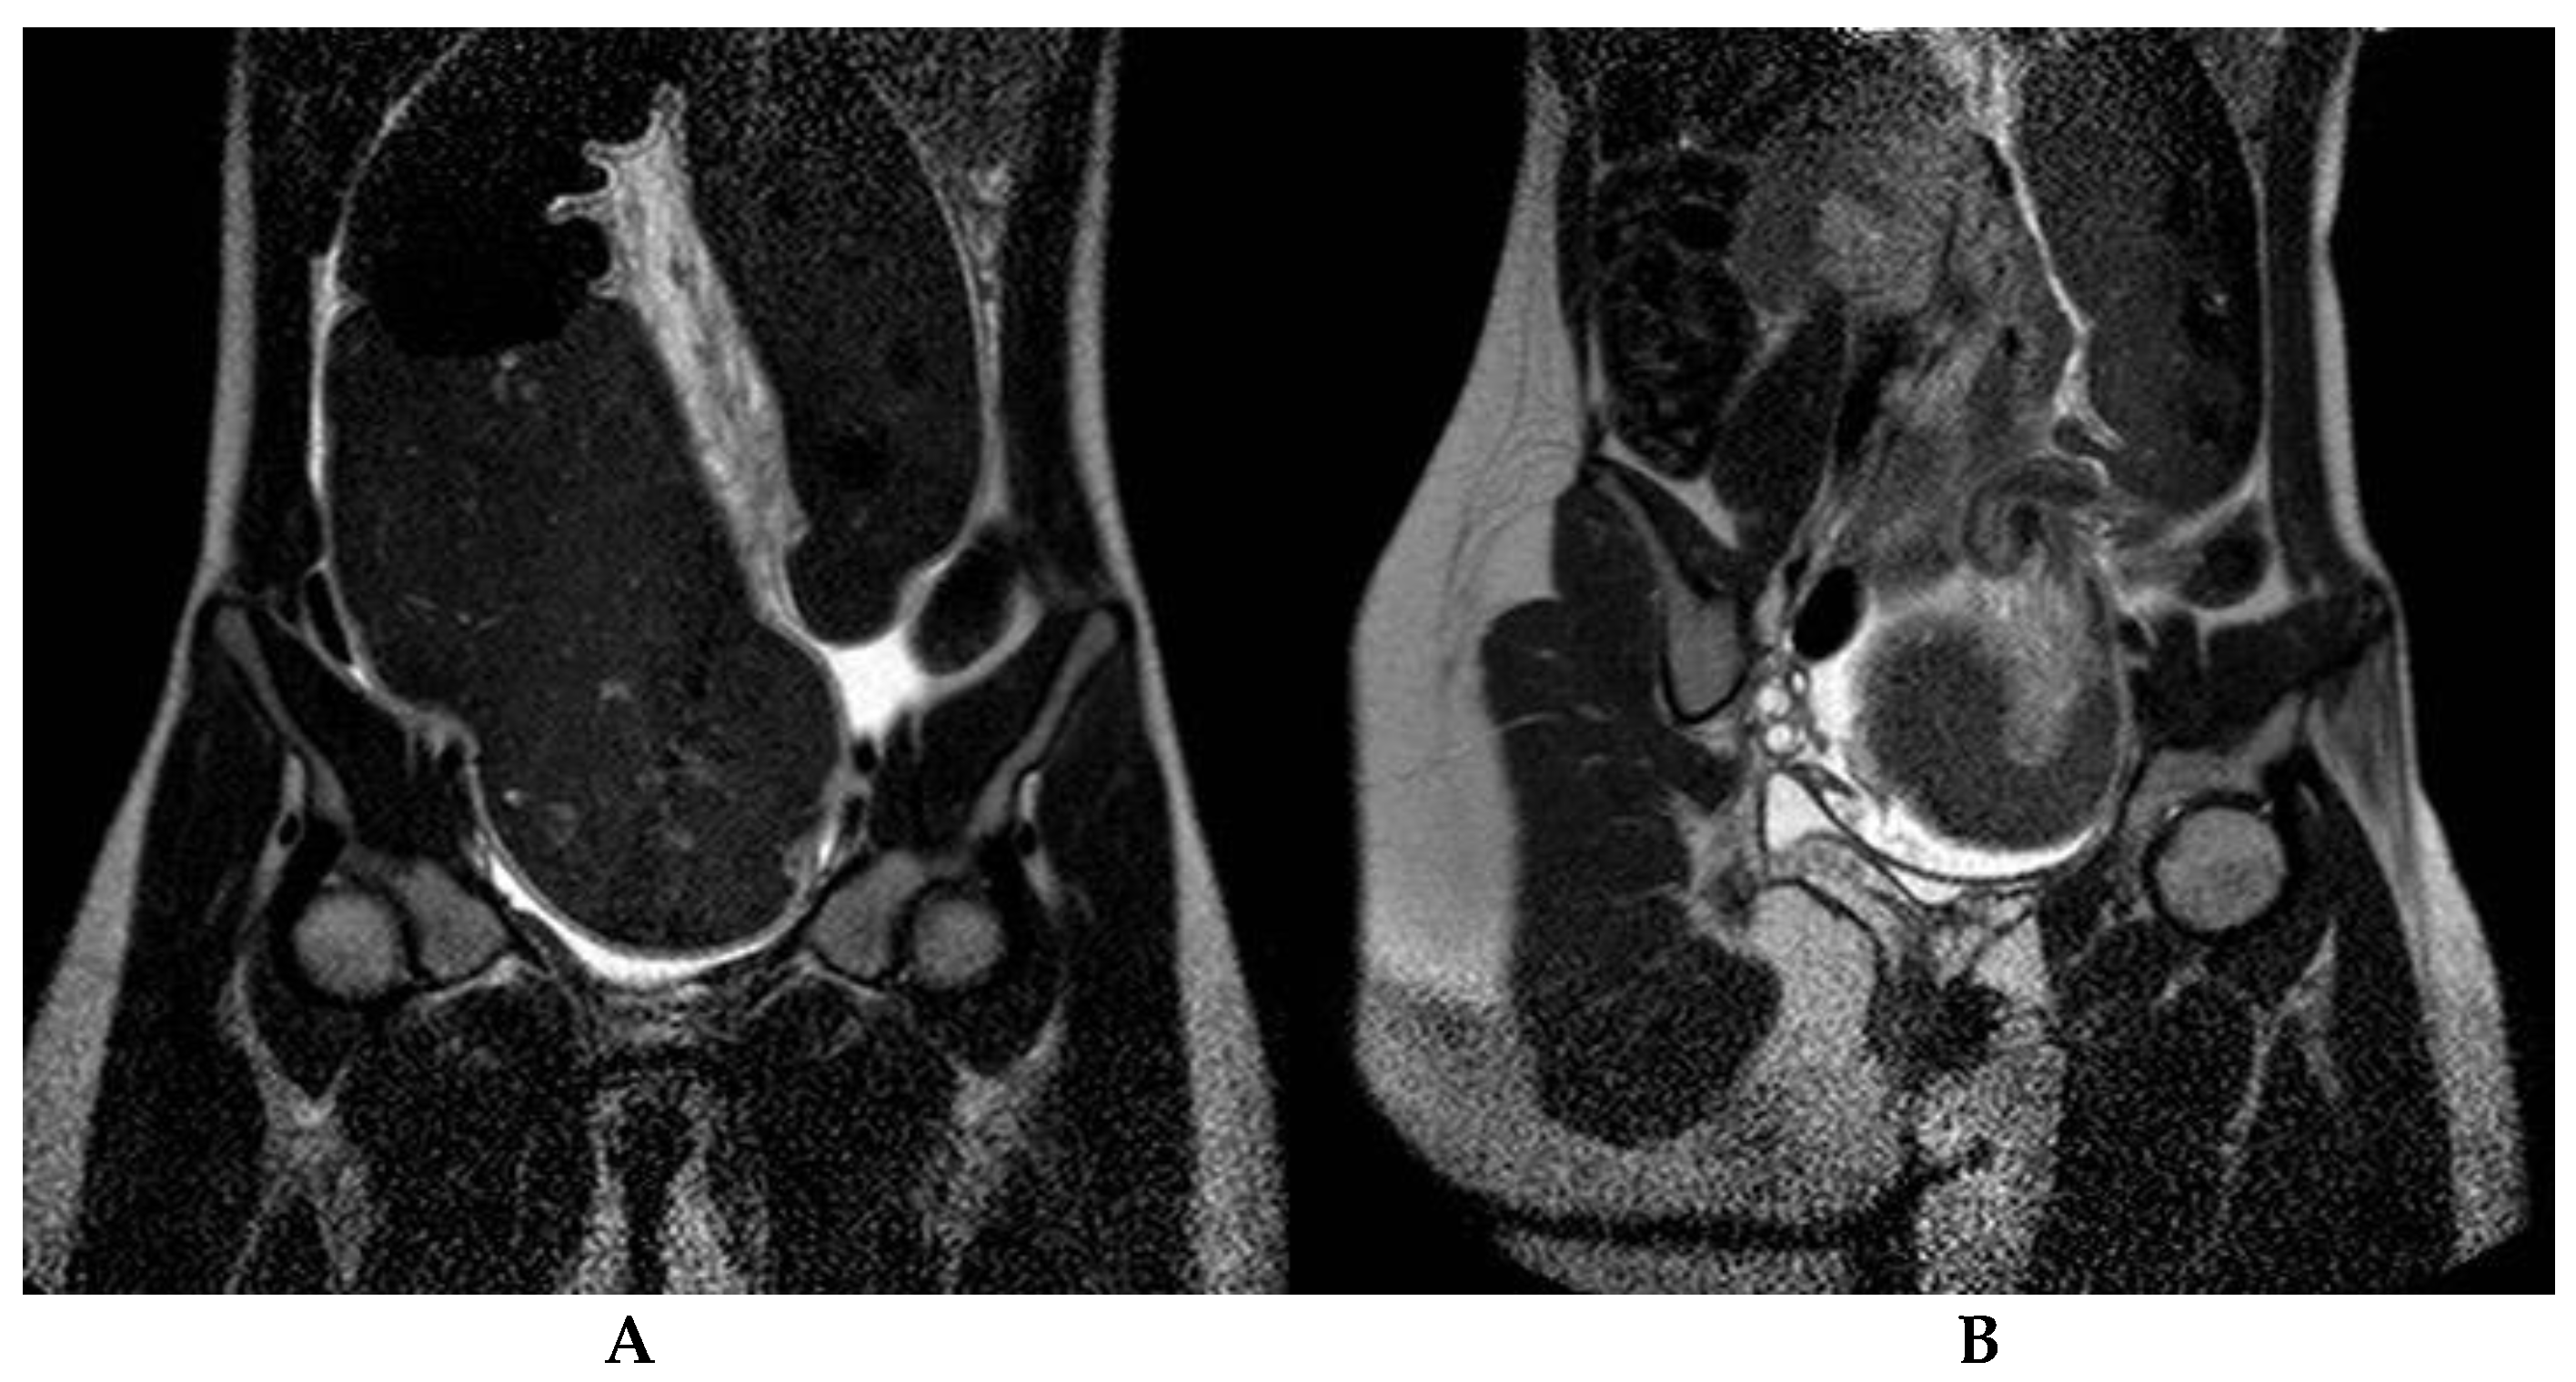

3.2. Instrumental Results